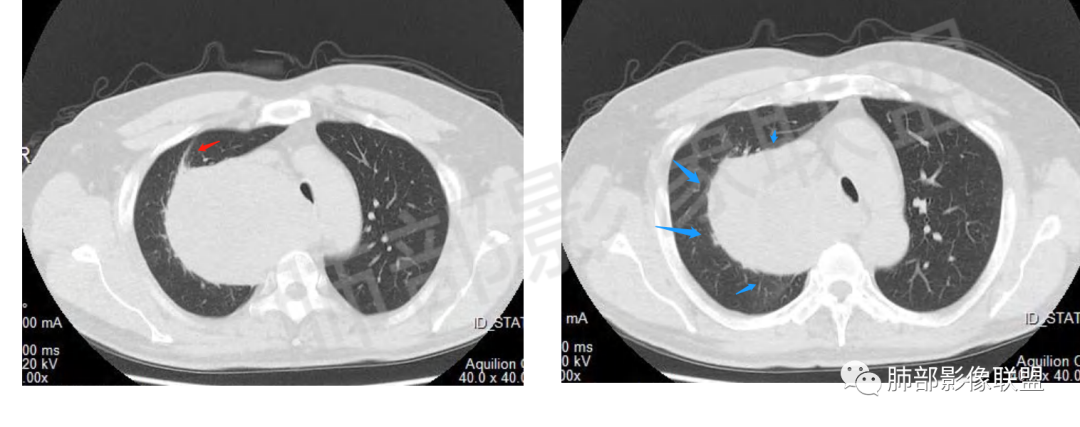

男,69岁,间断咳嗽4个月,右上肺体积缩小,可见巨大软组织占位,胸膜掀起,考虑来源于肺外,平扫密度不均匀,增强扫描明显不均匀强化,内部可见粗大血管及坏死区,周围组织受压移位。局部与食管分界不清,穿刺提示短梭形细胞,来源于间叶组织可能,综合考虑为神经鞘瘤>SFT

肿块把上腔静脉向前部推移,对肺内血管以及气管以推移为主,占位未见肺部血管供血,胸膜掀起处胸膜下脂肪间隙增宽,说明定位在肺外 SFT多为脏层胸膜起源,少部分壁层胸膜起源,壁层胸膜起源SFT不除外,但是胸膜掀起处胸膜下脂肪间隙增宽了,感觉SFT可能性比较小,这样囊变 AB区 纵膈神经起源的神经鞘瘤需要重点考虑,因为CT给的层不够,看不到肿瘤与椎间孔的关系,不敢确定,曾经病理提示高度考虑叶间起源肿瘤,肿瘤细胞呈短梭形细胞构成 不知道和神经鞘瘤是否符合!我重点考虑神经鞘瘤

边界清楚、光滑,D字征,与肺血管、支气管关系不密切,胸膜被掀起都提示肺外来源

粗大强化血管,主要看他起源,如果是来源肺动脉,肺内血管供血一是肺内二是脏层胸膜,肺内排除,只剩脏层胸膜SFT;如果这个是纵隔供血,那它可能是神经源性或者壁层胸膜,也可以是SFT比较少